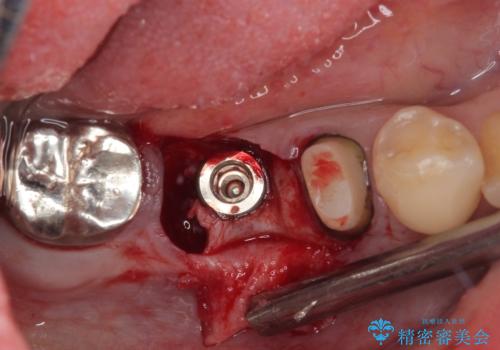

左下小臼歯は根管治療で対応する予定でしたが、診断のために歯肉を開いたところ頬側に垂直破折が認められたため、抜歯即時埋入インプラントによる補綴治療を選択することとしました。

インプラント埋入時に十分な安定値を得ることができたため、速やかに仮歯を装着し、最小限の通院回数で治療を終えることができました。